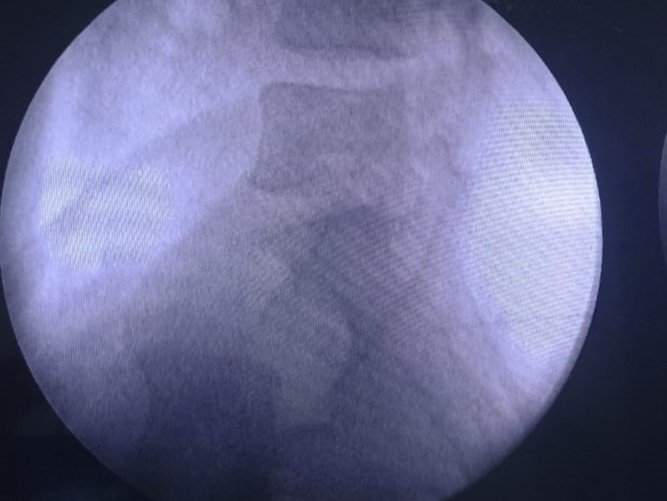

Patient undergoing Caudal Epidural Injection